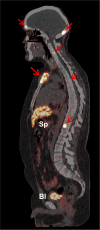

FIGURE 5.

PET/CT sagittal section of patient 1 at 60 min after injection of 68Ga-DOTATOC. Pathologic uptake was seen in multiple skeletal metastases (sternal manubrium, left orbital part of frontal bone, occipital bone, and multiple vertebrae [red arrows]). Comparatively higher physiologic uptake of 68Ga-DOTATOC was observed in spleen (Sp). Accumulation of activity in urinary bladder (Bl) was seen because of renal excretion of radiopeptide.